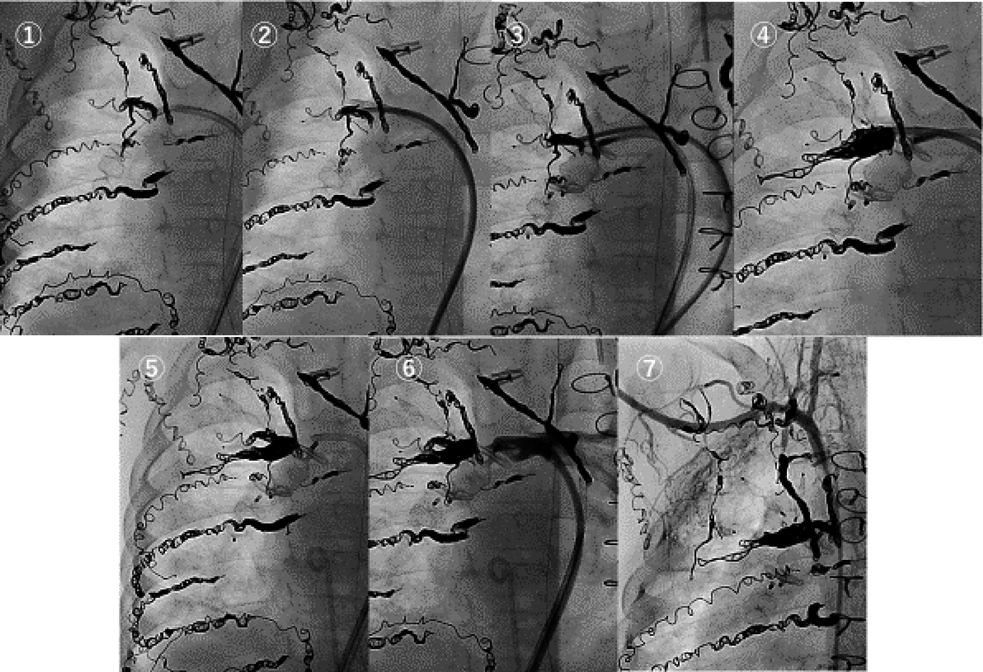

Fig. 6 Embolization of the right pulmonary artery

① An 8-mm AVP2 was placed for the right lower pulmonary artery (PA). ② A 5-mm AVP4 and 4-mm AVP4 were placed for the right upper PA. Additionally, we retained a multipurpose-type catheter in proximity to them. ③ We placed a 12-mm AVP2 in the right lower PA and retained it there without detachment from the catheter. ④ A 6-mm 40-cm coil and 5-mm 30-cm coil were placed between the right upper PA and lower PA using a multipurpose-type catheter. ⑤ We confirmed that a 12-mm AVP2 was placed to cover the coils and they did not escape to the right pulmonary artery and detached a 12-mm AVP2. ⑥ A right pulmonary artery angiogram demonstrated that the right pulmonary artery was not imaged at all and no superior vena cava stenosis was noted using a 12-mm AVP2. ⑦ A right subclavian artery angiogram demonstrated many aortopulmonary collateral arteries retained in the thorax because of right PA embolization.

最初にAngle付きシースから下葉枝遠位部に8 mmのAVP2を留置した.(Fig. 6①)

Parent Plusから上葉枝をAVP4 5 mm 2個と4 mm 1個で塞栓した.その近位部にMultipurpose typeカテーテルを配置した(Fig. 6②).

下葉枝に12 mmのAVP2を留置しdetachせずに(Fig. 6③)配置していたMultipurpose typeカテーテルから6 mm 40 cmコイルと5 mm 30 cmコイルを用いて上葉枝の細い枝と下葉枝の合流部を塞栓した(Fig. 6④).保持していた12 mmのAVP2が,この2つのコイルの近位部への流入を防止する形態になっていることを確認した.

Multipurpose typeカテーテル抜去し2つのコイルと12 mm AVP2がずれないことを確認しAVP2をdetachし手技を終了した(Fig. 6⑤).

右肺動脈造影では右肺動脈の順行性血流はなく左へ流入し(Fig. 6⑥),右鎖骨下動脈造影では体肺側副血管内に造影剤が停滞し左肺動脈への逆行を認めなった(Fig. 6⑦).塞栓後の平均中心静脈は16 mmHgであった(Table 3).

造影CTで右肺動脈の血管径と距離を計測,気管や食道など周辺組織との位置関係を確認した.デバイスが近接組織へ影響を与えない遠位側から右側上大静脈までの範囲を閉鎖する方針とした.血管径の小さい上葉枝にAVP4を,上葉枝と下葉枝合流部までは留置幅が短いためコイルを,下葉枝は太くて留置幅が大きいためAVP2を用いることとした(Fig. 5).